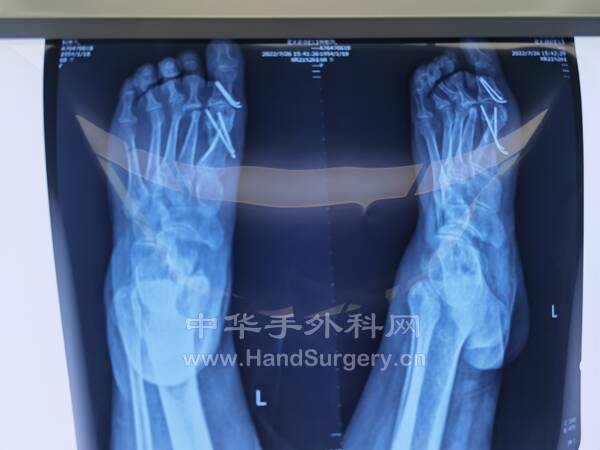

今日参与手术一台 (左足拇外翻),参观手术2台(拇外翻术后取内置物,双侧马蹄内翻足)

IMG_20220802_142713.jpg

IMG_20220802_082653_edit_928462598071868.jpg

IMG_20220802_131932_edit_928537719271336.jpg

IMG_20220802_082647_edit_928487634746864.jpg